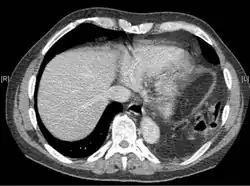

A tomografia computadorizada tem maior precisão diagnóstica que a radiografia,[7] mas não há achados específicos na tomografia que confirmem o diagnóstico.[9] A borda livre de um diafragma rompido pode se enrolar e ficar perpendicular à parede torácica, um sinal conhecido como diafragma pendente. Um órgão herniado pode se contrair no local da ruptura, um sinal chamado de sinal do colar. Se o fígado hernia através de uma ruptura à direita, pode produzir dois sinais conhecidos como sinal da corcova e sinal da banda. O sinal da corcova é uma forma do sinal do colar à direita. O sinal da banda é uma linha brilhante que atravessa o fígado, acreditada como resultante da compressão pelo diafragma rompido.[13] Embora a tomografia aumente as chances de diagnóstico pré-cirúrgico de ruptura do diafragma, a taxa de diagnóstico antes da cirurgia ainda é de apenas 31–43,5%.[7] Outro método diagnóstico é a laparotomia, mas ela falha em detectar rupturas do diafragma em até 15% dos casos.[4] Frequentemente, a lesão do diafragma é descoberta durante uma laparotomia realizada por outra lesão abdominal.[4] Como as laparotomias são mais comuns em traumas penetrantes do que em traumas contusos, a ruptura do diafragma é encontrada com maior frequência nesses casos.[14] A toracoscopia é mais confiável para detectar rupturas do diafragma do que a laparotomia e é especialmente útil quando se suspeita de hérnia diafragmática crônica.[4]